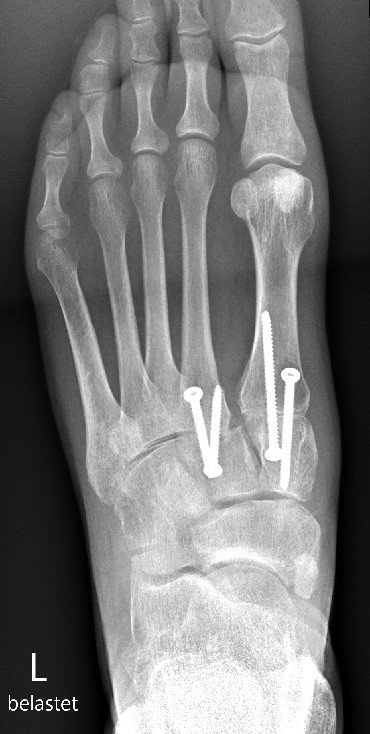

Wir veranlassten ein operatives Vorgehen mittels Arthrodese der Lisfranc 1- und 2-Gelenke (Versteifung des 1. und 2. Mittelfussgelenkes), Abb. 5. Bereits 2 Monate nach der Operation konnte die Patientin ihren Alltag wieder ohne grössere Schmerzen durchführen. Es ist davon auszugehen, dass sportliche Aktivitäten ebenfalls in absehbarer Zeit wieder möglich sein werden.